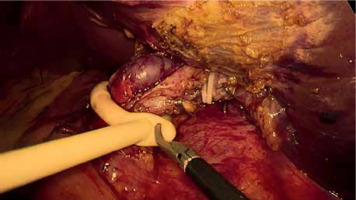

PM should be prepared before parenchymal transection for possible immediate application. It can be performed intracorporeally and extracorporeally. For an intracorporeal PM a long cotton tape is placed around the hepatoduodenal ligament through a 12 mm trocar, then passed through a small tourniquet and clipped 2–3 cm above it. For occluding the hepatic inflow, the tourniquet is pushed toward the hepatic pedicle and clipped above it. Pedicle clamping may also be performed with a laparoscopic bulldog clamp or appropriately prepared Foley’s catheter (Photo 3) [22]. For an extracorporeal PM the tape is externalized through a trocar and passed through the catheter placed above the trocar. The main advantage of the extracorporeal technique is the possibility for clamping by the assistant surgeon, without distraction of the main surgeon (Photo 4). When comparing both techniques of PM in retrospective studies, extracorporeal PM carries more practical advantages, but it still requires further research [23]. PM can be continuous or intermittent (most commonly 15 : 5 min ratio or 10 : 5 min ratio in cirrhotic liver). In HCC patients, according to a recent RCT, 25 min intermittent PM results in lower BL, as well as higher transection speed [24]. However, the performed PM technique depends on surgeons’ preferences and estimated operative time.